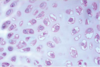

What 2 cell types are found in cartilage?

1) Chondroblasts -> replicating population of cells that secrete cartilaginous matric

2) chondrocytes -> maintain the matrix

What cell type found in cartilage is often found in groups of 2-8 cells (isogenous groups)?

Chondrocytes